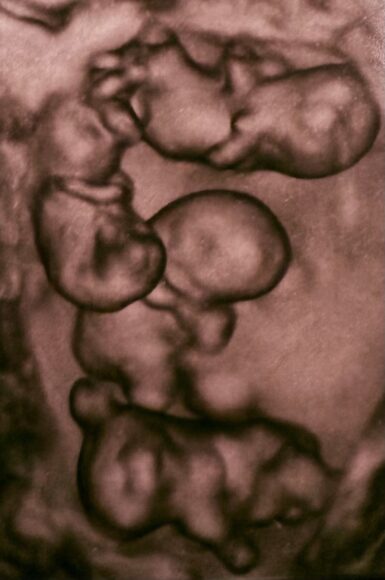

В петербургском роддоме – впервые в России – приняли однояйцевую четверню. На свет появились четыре сестренки

Уникальные роды прошли 2 апреля в Санкт-Петербурге: женщина произвела на свет четверняшек – девочек, развившихся из одной оплодотворенной яйцеклетки.

В роддоме №17 на Леснозаводской улице, где принимали роды, назвали это «чудом в четвертой степени». По статистике монохориальная (однояйцевая) четверня получается в одном случае на 15,5 миллиона родов. В России такой случай произошел впервые.

На свет появились, одна за другой, четыре очаровательных девочки. Их показатели, по оценке врачей, прекрасны для неполного срока, который они провели в материнской утробе: 1400 граммов и 38 сантиметров, 1570 г и 41 см, 1640 г и 41 см, 1360 г и 37 см.

Фото: vk.com/rdom17